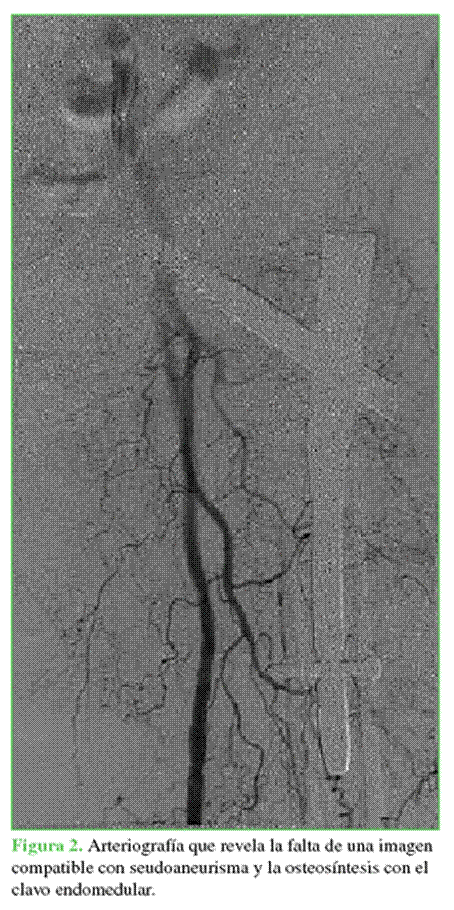

La paciente fue derivada a un hospital de referencia para ser examinada por Cirugía Vascular. El 28 de septiembre de 2018, se le practicó una arteriografía del sector femoral izquierdo por vía femoral derecha con la intención de realizar la embolización del seudoaneurisma en el muslo, no se identificaron imágenes arteriográficas compatibles con aneurismas en el sector femoral (Figura 2).